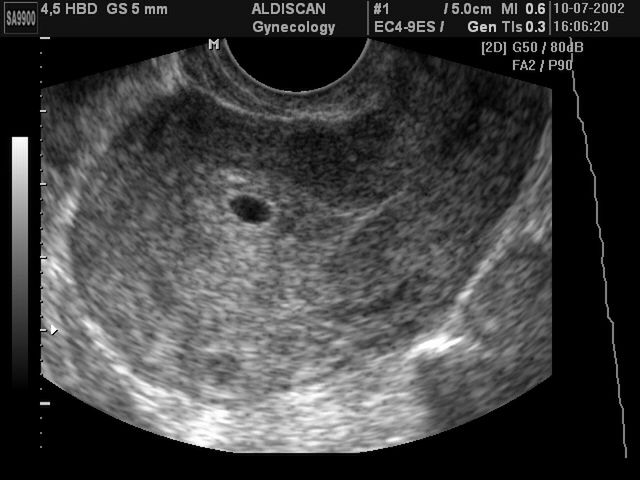

Płód w 5 tygodniu ciąży

W 5 tygodniu zaczyna kształtować się mózg oraz kręgosłup dziecka

/ 1Płód w 5 tygodniu ciąży - długość płodu

Pod koniec 5-go tygodnia dziecko będzie miało ok. 2 mm